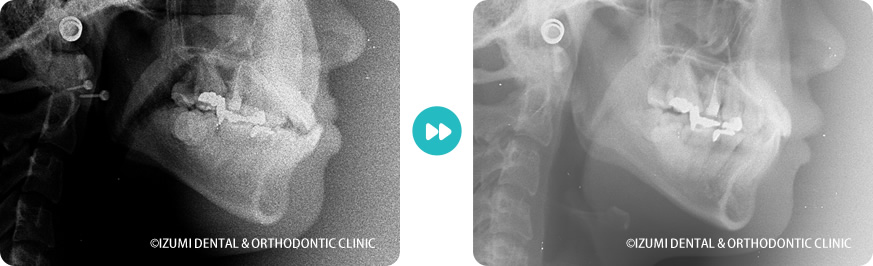

外科(骨切り)処置を回避できた症例02

| 診断名 | Ⅲ級顎偏位 |

| 治療内容・装置 | 多数の歯科医院で外科矯正を勧められた症例です。インビザラインでは受け口の症例は少ないですが、マウスピースの装着時間やチューイの使用など、当院のご案内どおり頑張って頂いたおかげで外科処置をすることなく治すことができました。 |

| 抜歯の有無 | 下顎右側第一小臼歯 |

| 治療期間 | 1年11ヶ月 |

一般的には外科処置が必要なとても難しい症例です。こちらの指示通りにマウスピースの装着・チューイを行っていただけない場合は治療が困難となります。 |